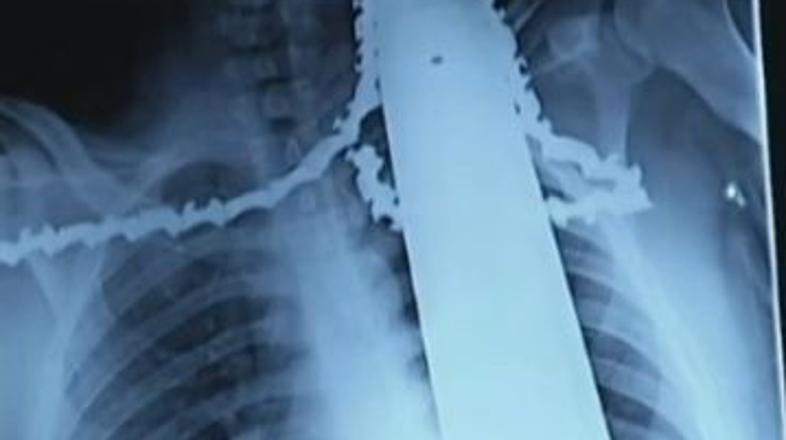

Motorka se mu je zarila v ramo in vrat

21-letni delavec se je ponesrečil z motorno žago, ki je pristala v njegovi rami in vratu.

Obrezovalec dreves James Valentine iz Pensilvanije je lahko srečen, da je živ. Med obrezovanjem drevja se mu je namreč motorna žaga nekaj centimetrov globoko zarila v ramo in vrat. Z žago v telesu so ga tudi pripeljali v bolnišnico.

Nesreča se je zgodila med običajnim delom na drevesih. V nekem trenutku je žaga poskočila nazaj in zarezala v njegovo telo. Delavci so nesrečneža spustili z drevesa, mu odstranili žago, rezilo pa pustili v telesu, da ne bi izgubil še več krvi. Nato so ga odpeljali v bolnišnico, kjer so ga takoj operirali.

"Bil je zelo razburjen, a ni bil v smrtni nevarnosti. Dobro se je držal, ni jokal in ni izgubil samonadzora," so povedali zdravniki. Na srečo je rezilo zgrešilo vse vitalne dele in je poškodovalo le ramenske mišice. Zdravniki pričakujejo, da bo popolnoma okreval.